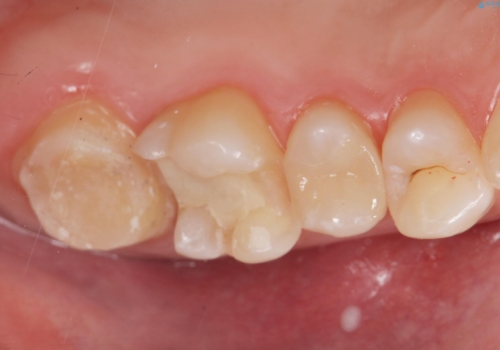

奥歯の虫歯の治療

- 奥歯が虫歯になっていたため治療しました。

手前側の歯は前から見えるため、セラミックの詰め物で治療しました。

奥は高さを取るのが難しかったため薄く作れる金属(ゴールド)で治療しています。

- 合計 26.4万円(内訳:右上7 PGAクラウン 11万円(旧料金)、右上6PGAインレー 7.7万円(旧料金)、右上5 emaxインレー 7.7万円)費用は治療当時の料金となります

今後の虫歯予防に、治療と合わせて歯磨き指導も行っているため、清掃状態も大きく改善しています。